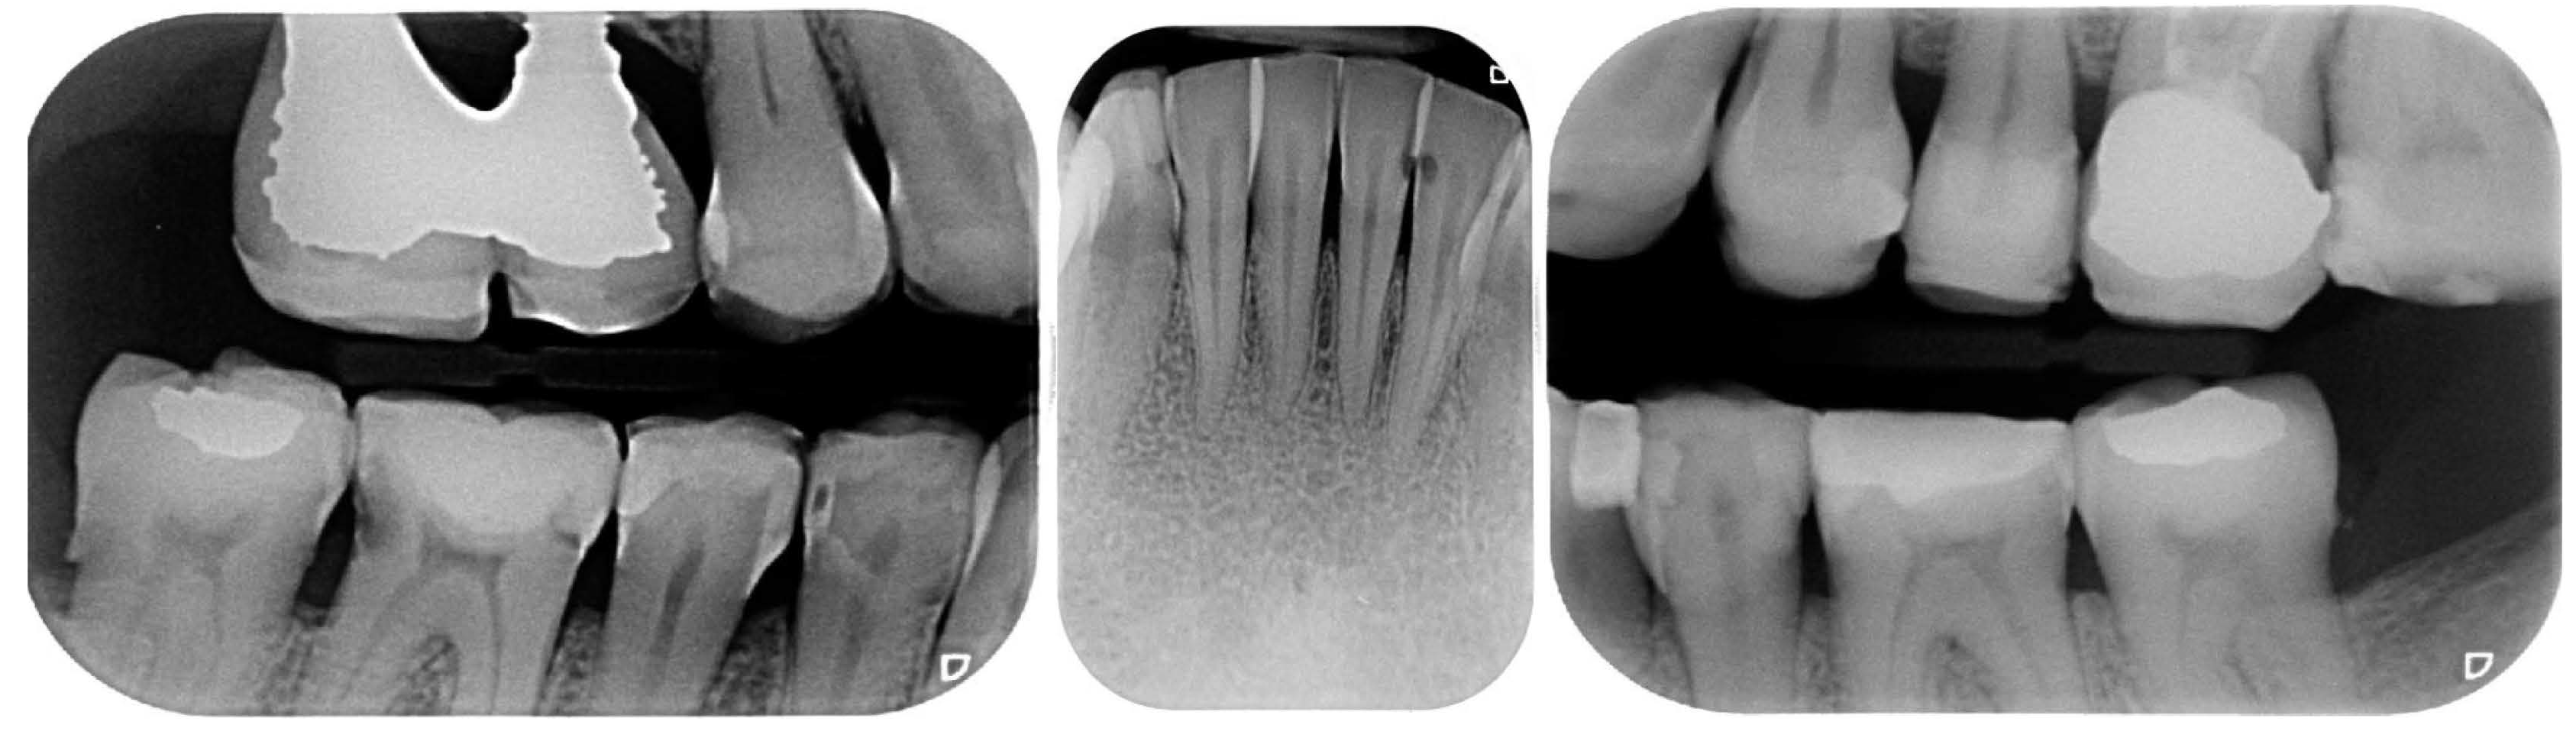

2.2. Clinical Example